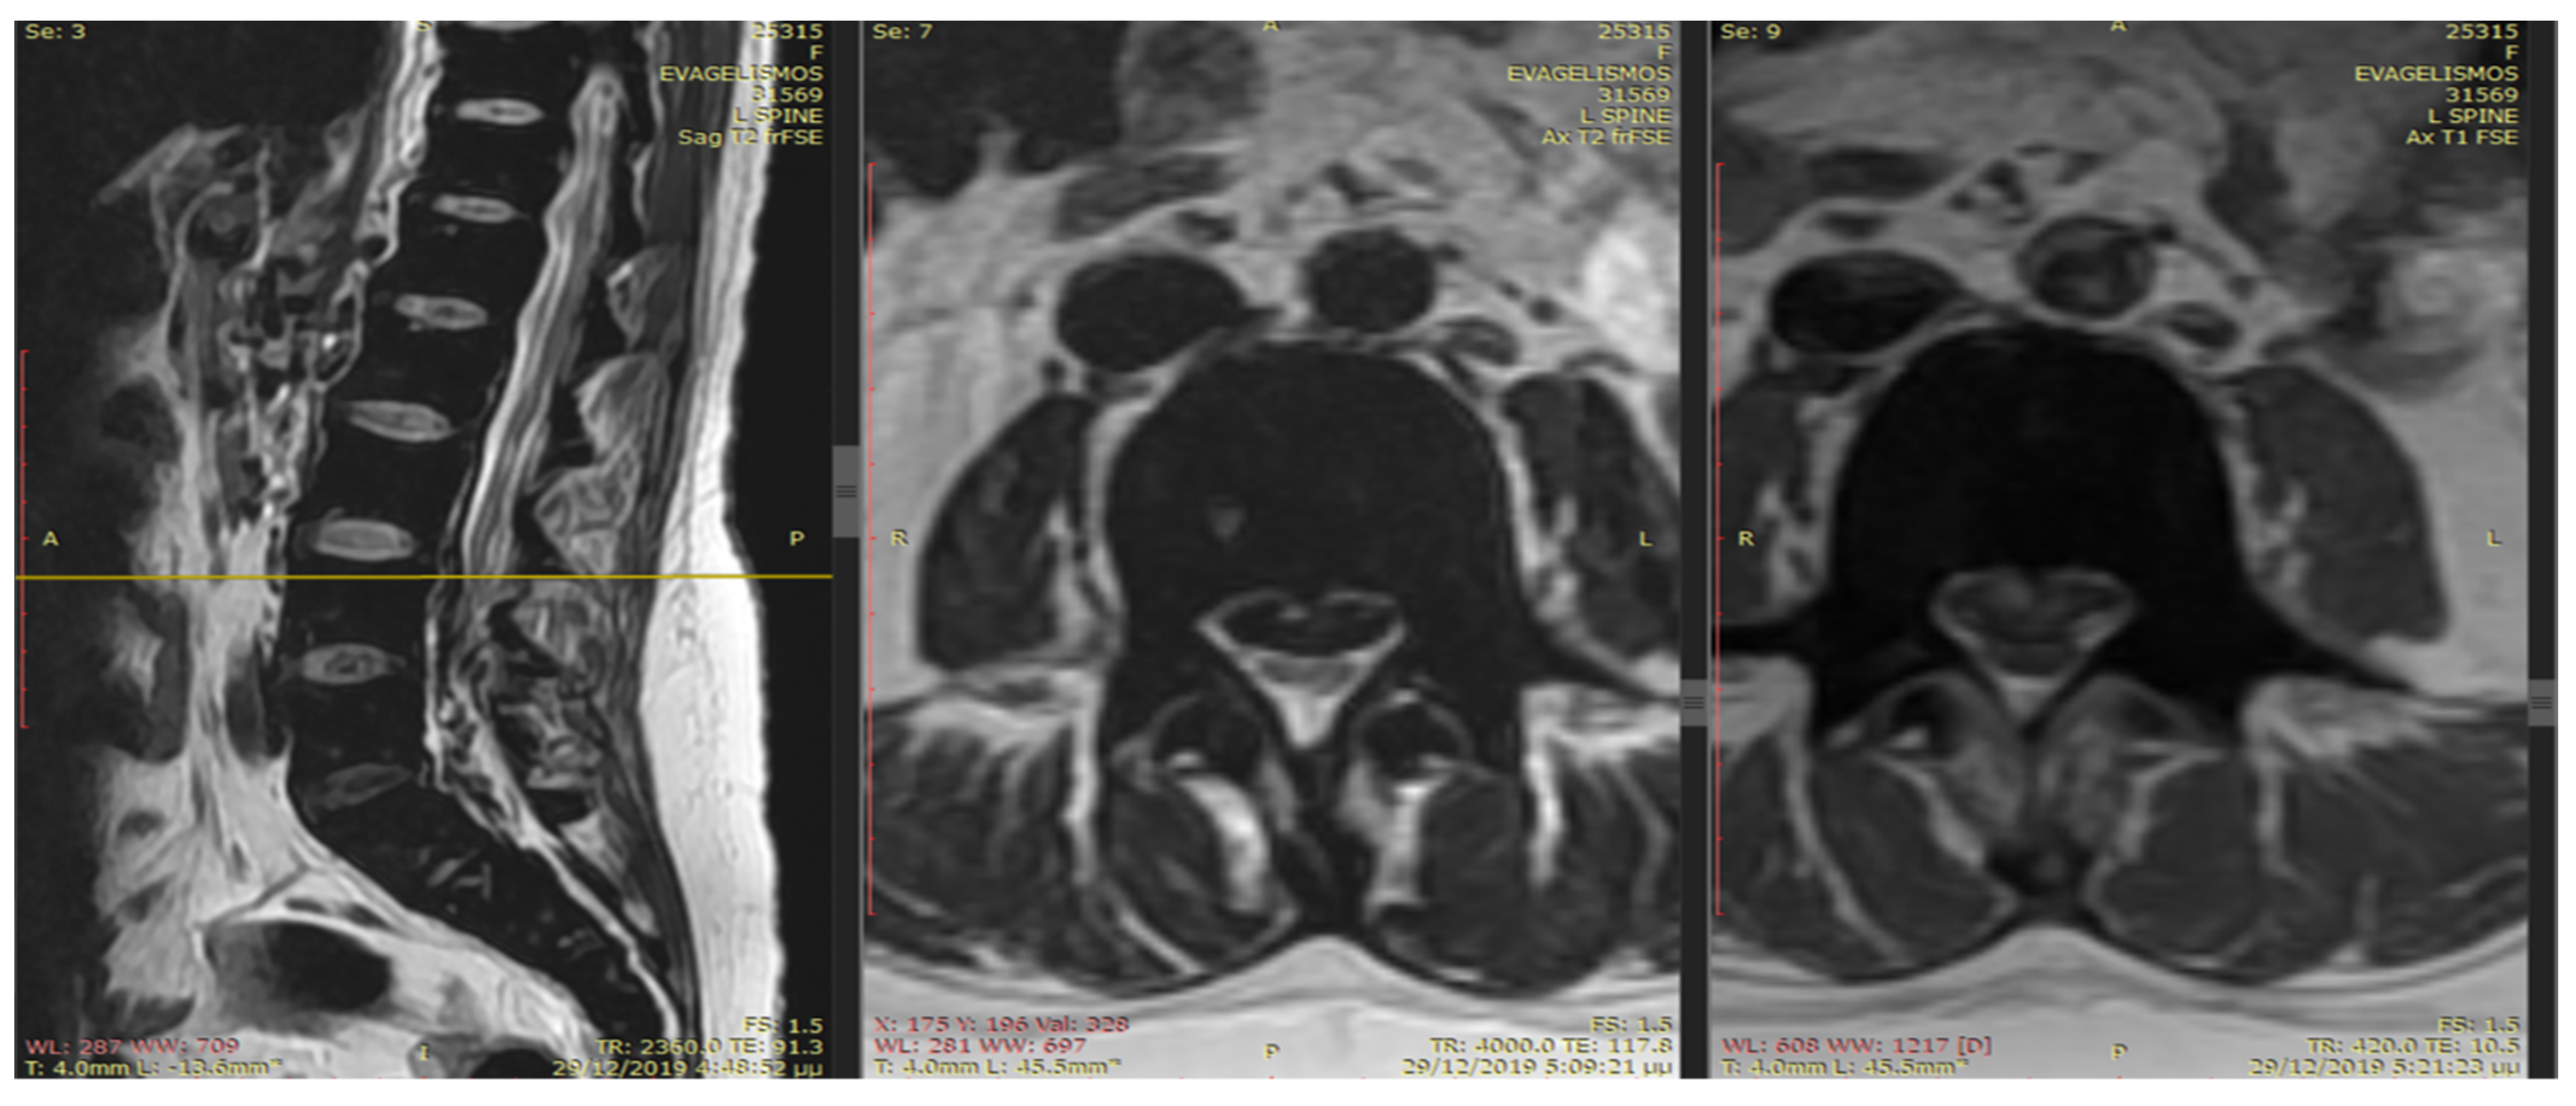

An emergency MRI was conducted on the patient, and the findings can be succinctly summarized as follows. In the T2 sequence, a low signal is observed in the anterior epidural space, accompanied by an uneven signal in the T1 sequence. These observations indicate compressive effects on the dura at the level of L2, extending towards the posterior segments of the spinal canal up to the final segment. Furthermore, a portion of this compression appears to extend along the midline fissures on the right side, particularly at the levels of L5–S1 and S1–S2, causing mild compressive effects on the nerve roots. In the GRE sequence, a low signal is noted in a segment of the aforementioned distribution, raising strong suspicion of hemosiderin deposition (Figure 1 and Figure 2). In the fat-suppressed T2 sequence, there is a diffuse increase in signal, signifying edema, in the soft tissues at the level of the midline fissures in the posterior elements and the soft tissues between the ligamentum flavum and the dura at the intervertebral foramina level. Additionally, edema is observed in the epidural space.

Figure 1.

In the T2 sequence, there is a low signal in the anterior epidural space, along with an inhomogeneous signal in the T1 sequence. These findings suggest compressive effects on the dura at the level of L2, extending to the posterior parts of the spinal canal until the final segment. Additionally, a segment of this compression seems to extend along the course of the midline fissures on the right side, specifically at the levels of L5–S1 and S1–S2, causing mild compressive effects on the nerve roots.